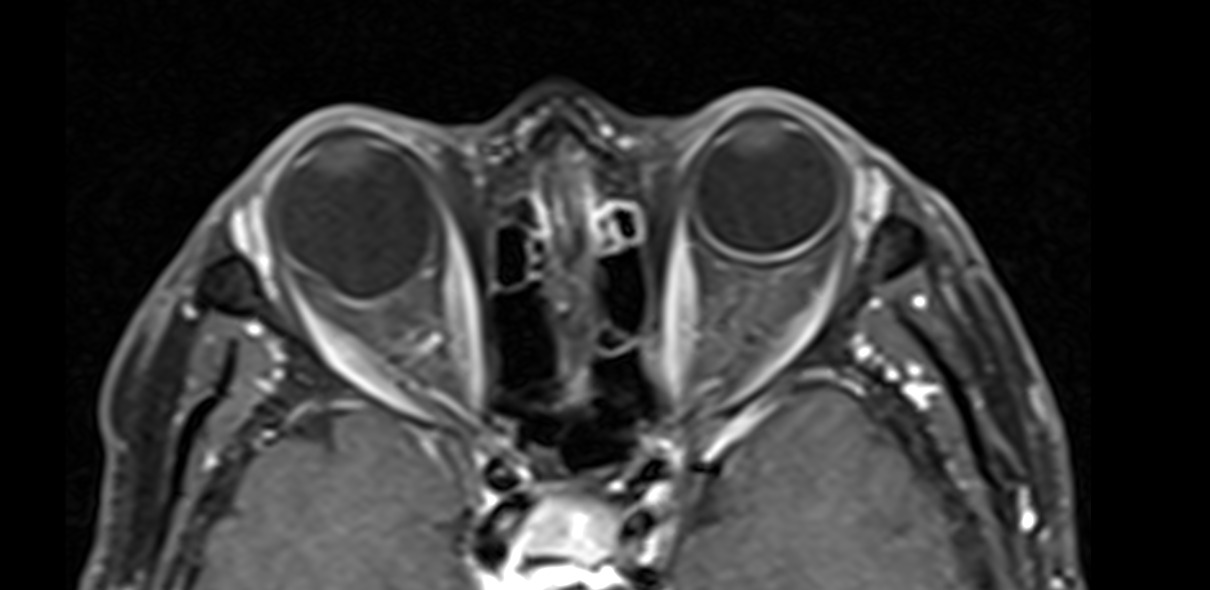

Cortes axiales de resonancia magnética de órbitas en el cual se aprecia aumento del tamaño del globo ocular derecho a expensas de su eje anteroposterior, acompañado de adelgazamiento de su pared posterior lo cual corresponde a estafiloma.

Definición: Adelgazamiento y estiramiento de las capas escleral-uveal del globo ocular.

Hallazgos por imagen: Aumento del tamaño del globo ocular y adelgazamiento de sus paredes posteriores.